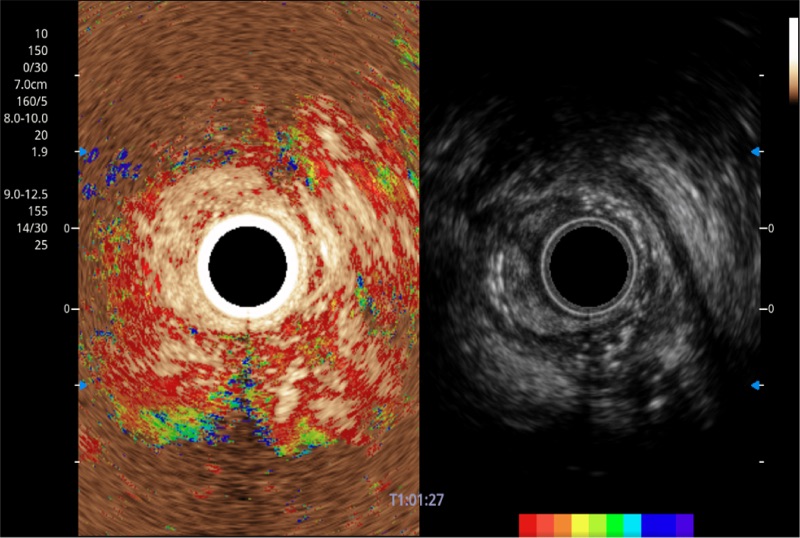

可人为将灰阶图像转变成彩色的显示方式,增强人眼对于不同回声强度的敏感度,主观上增加了图像分辨率

微米成像技术提升了对组织斑点噪声信号的抑制能力,并进一步强化边界信息,从而获得信噪比更优、边界更清楚锐利的图像

清晰显示胆总管及周围血管分布